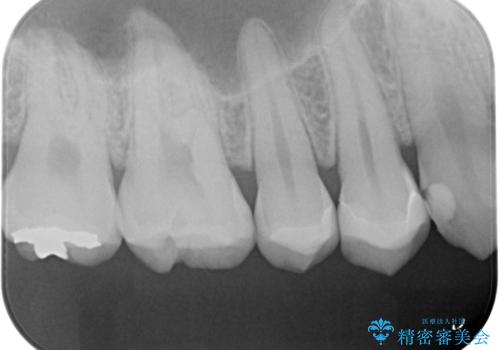

- 銀の詰め物をやりかえたいとの事で来院。

詰め物を外し、虫歯がない事を確認してからe-maxインレーで治療しました。

白く、適合の良い詰め物が入りました。セラミックは汚れや細菌付着しにくいので虫歯の再発のリスクが低くなります。